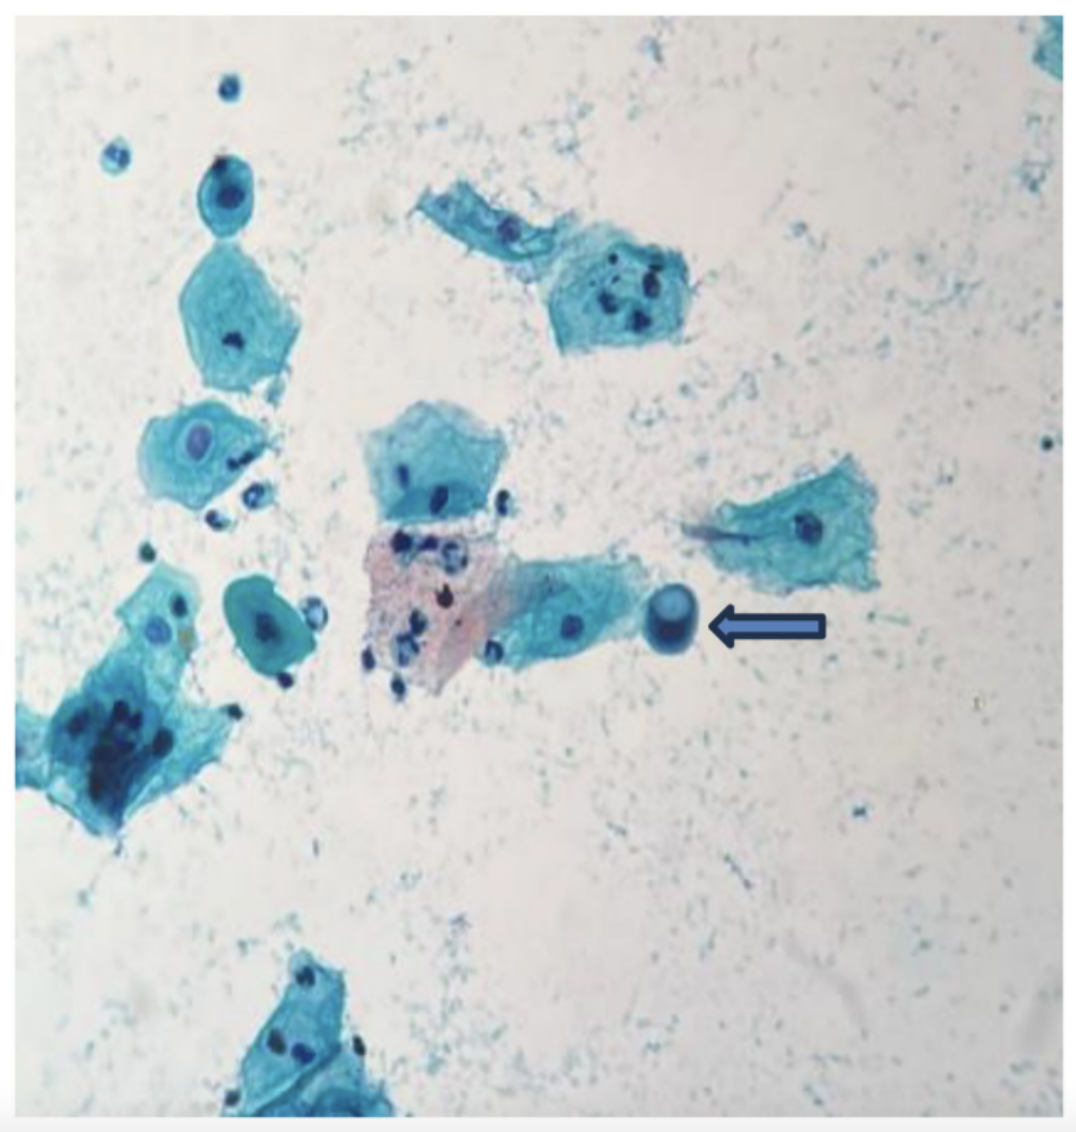

Rare Sciatic Nerve Tumor in Child Successfully Treated with Microsurgery

“This case underscores the importance of meticulous surgical technique, the potential value of IONM, and vigilant postoperative care in achieving optimal outcomes for deep-seated pediatric neurofibromas.” BUFFALO, NY — January 21, 2026 — A new case report was published in…